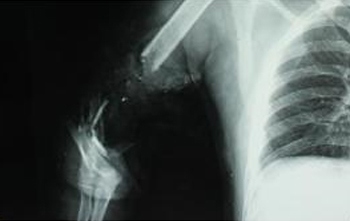

在尹烈教授、黃東院長等技術(shù)指導(dǎo)下,喻田主任帶領(lǐng)的年輕醫(yī)護(hù)團(tuán)隊持續(xù)開展了各類手外科重大復(fù)雜手術(shù),在肢體離斷再植、嚴(yán)重肢體創(chuàng)傷保肢、四肢大創(chuàng)面游離皮瓣修復(fù)、骨感染、骨缺損的顯微修復(fù)重建等方面達(dá)到了國內(nèi)外先進(jìn)水平。

近年來,科室積極開展應(yīng)用踝關(guān)節(jié)鏡、Irizarov技術(shù)、微創(chuàng)截骨等新技術(shù)治療踝關(guān)節(jié)運動損傷、踝關(guān)節(jié)不穩(wěn)、足踝部先天性及后天性畸形、扁平足、高弓足、踇外翻等疾病,利用淋巴管-靜脈吻合術(shù)(VLA)、血管化淋巴結(jié)跨體區(qū)皮瓣移植術(shù)(VLNT)治療原發(fā)、繼發(fā)性淋巴水腫,技術(shù)水平日漸精進(jìn),取得了可喜的成績。